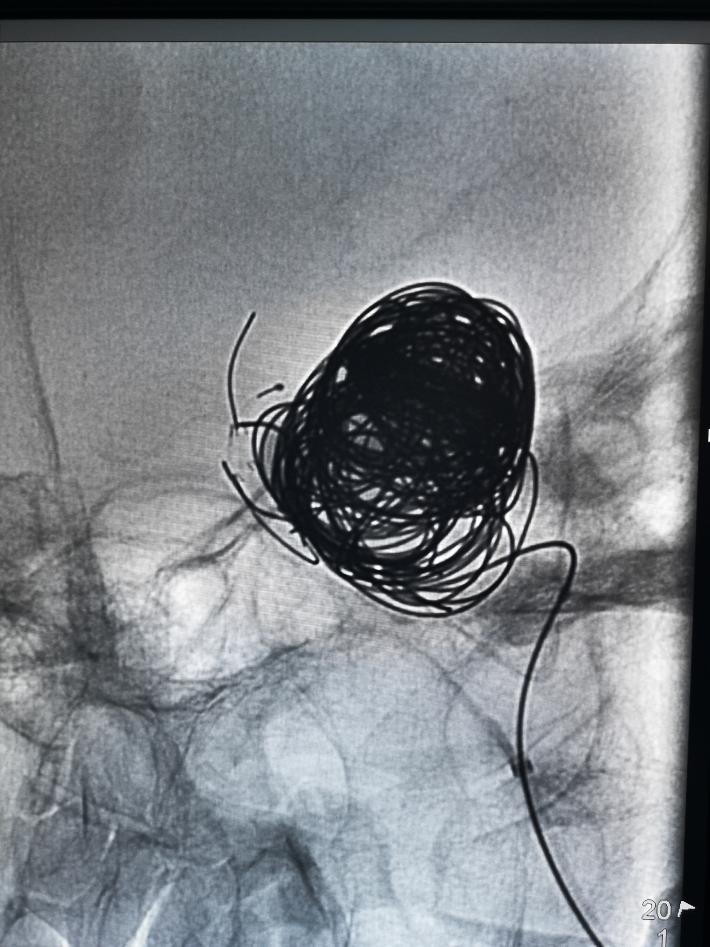

术中我们在密网支架导管无法到位的情况下,选择了常规的“支架辅助下动脉瘤介入栓塞术”,动脉瘤顺利得以治疗,由于瘤体巨大,且患者经济原因,无法做到致密填塞。

术后正侧位造影见,瘤体基本不显影,远端血流流速基本无延迟。

术后患者已平安出院,视力无影响,但眼征仍存在。